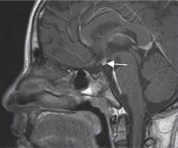

El resultado de la RNM fue ausencia de representación del infundíbulo-tallo hipofisiario, así como de la neurohipófisis en el nivel intraselar por el presente método de estudio. Adenohipófisis disminuida de altura sin lesiones focales. Imagen con aspecto de neurohipófisis ectópico (Figura 1). Estos hallazgos sugieren el SITH.

Figura 1 RNM de hipófisis con contraste (gadolinio), corte sagital: adenohipófisis disminuida de altura sin lesiones focales